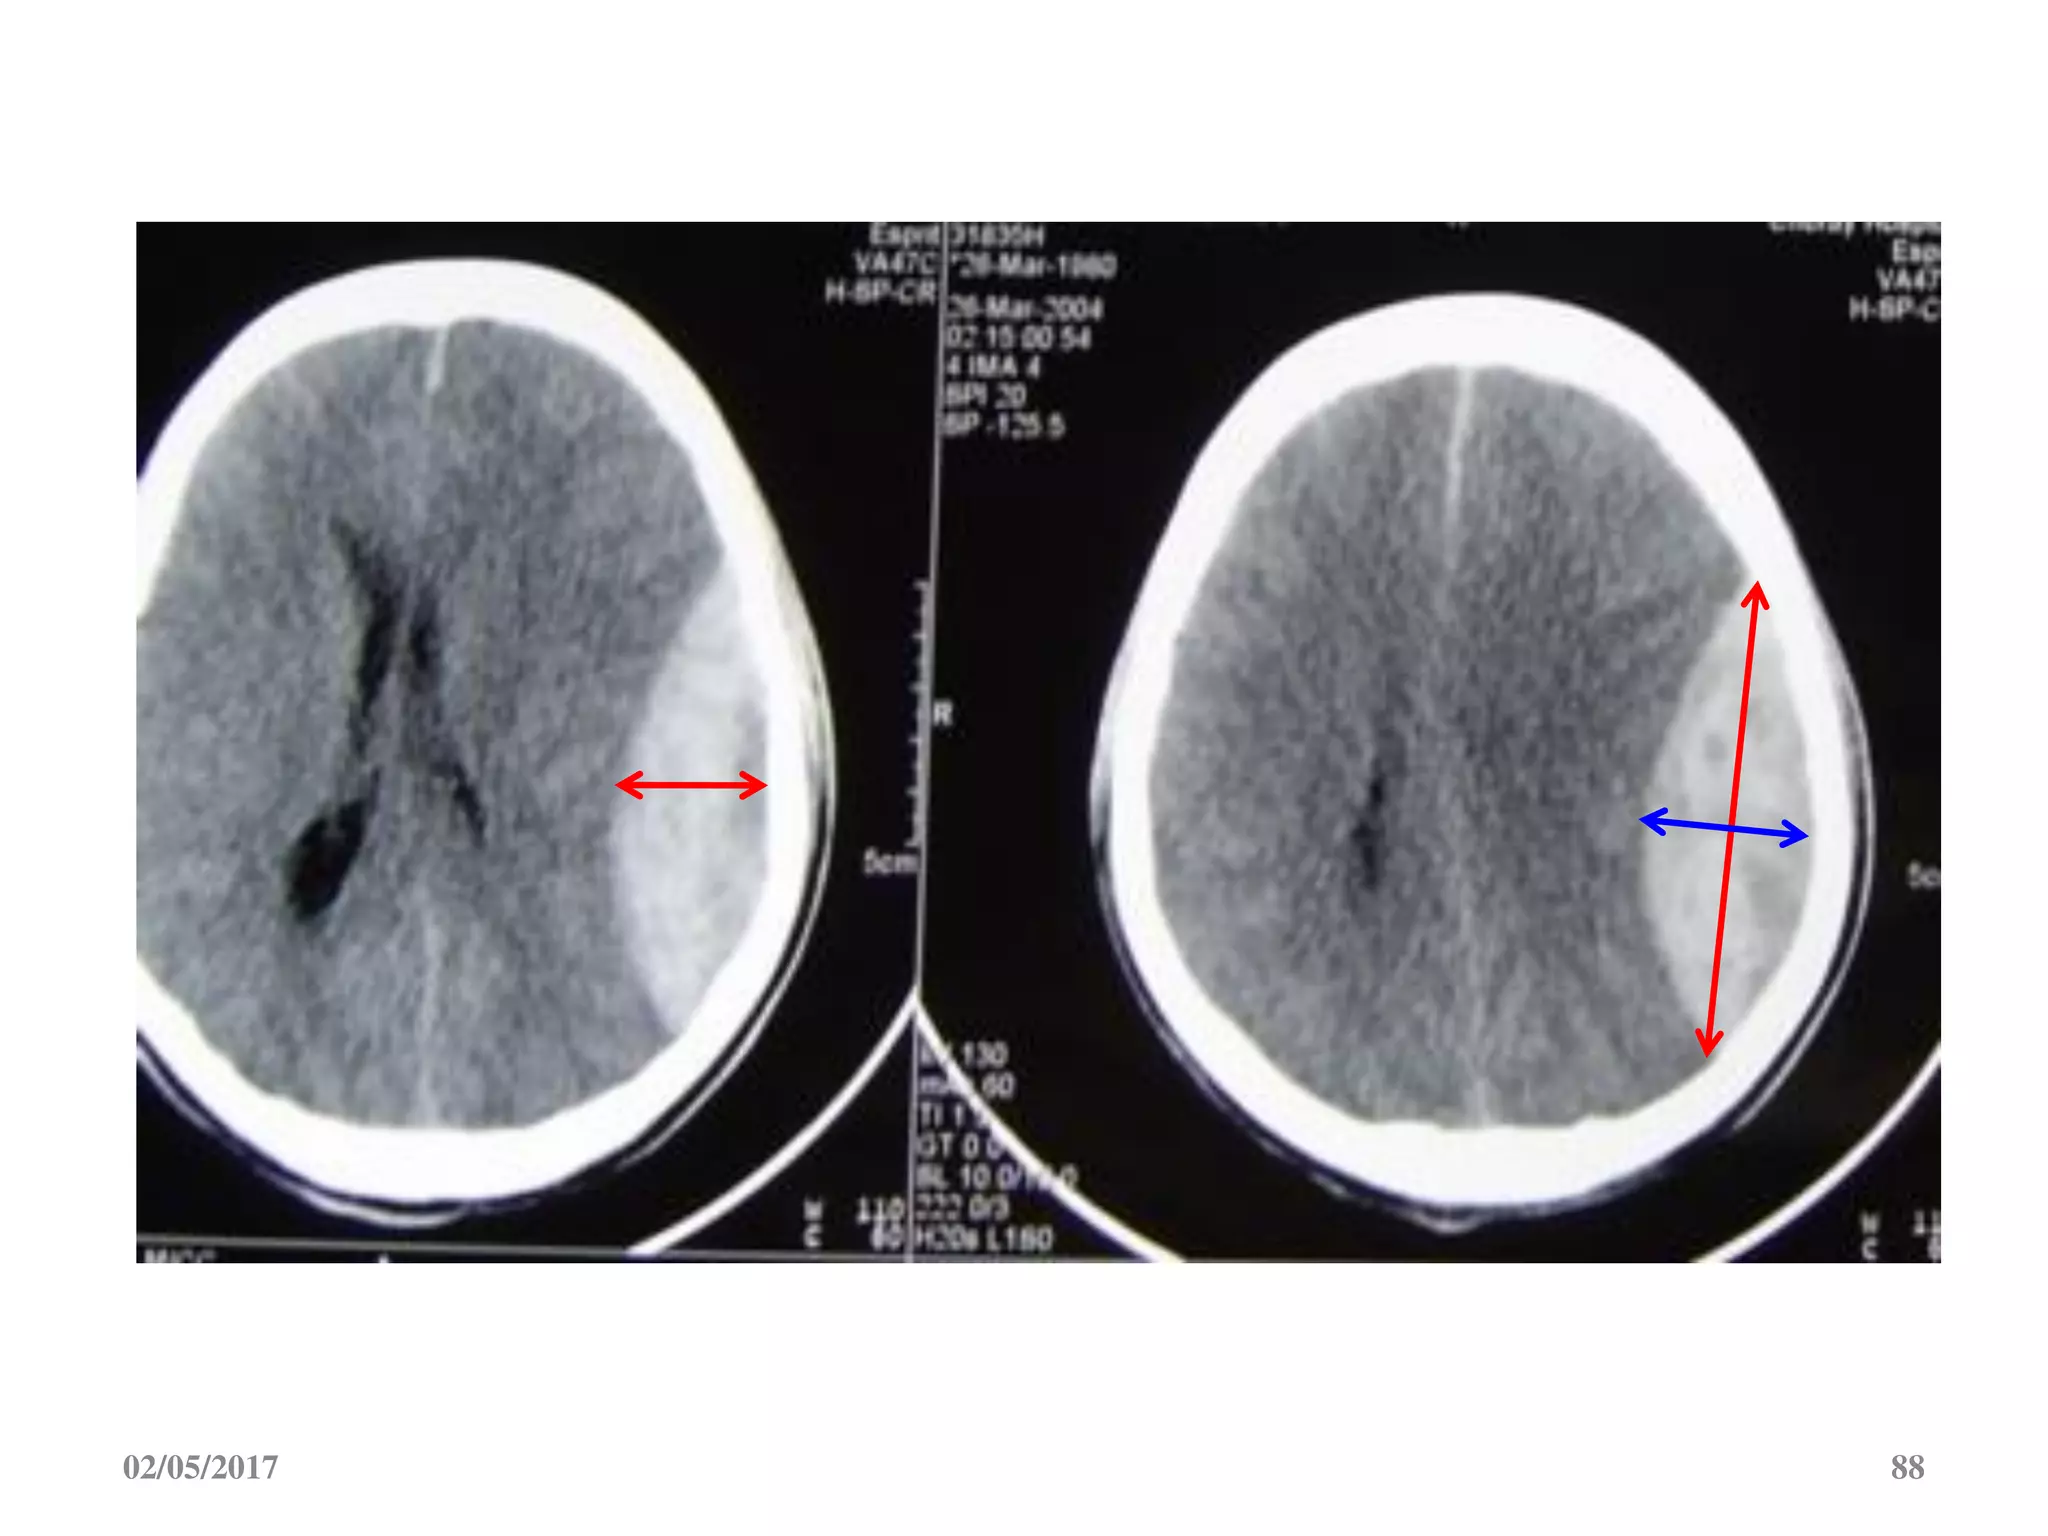

Dập não

• Vị trí: hay gặp ở trán

và thái dương.

• Cùng bên hoặc đối

bên với vị trí tác động

trực tiếp.

• Hình ảnh giảm đậm

độ do phù khu trú lẫn

tăng đậm độ do xuất

huyết rãi rác

Dập não • Vịtrí: hay gặp ở trán và thái dương. • Cùng bên hoặc đối bên với vị trí tác động trực tiếp. • Hình ảnh giảm đậm độ do phù khu trú lẫn tăng đậm độ do xuất huyết rãi rác 02/05/2017 66